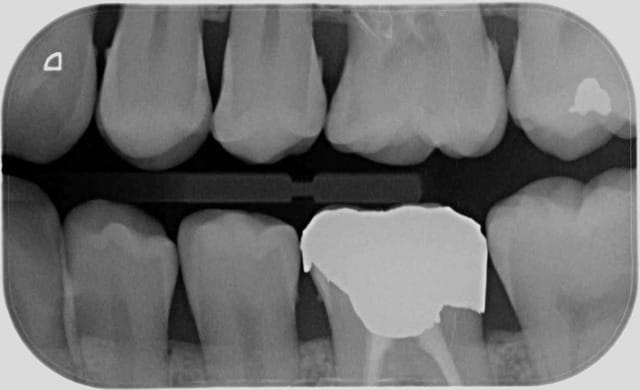

Comment vous cotez ca ?

( au passage rétro alvéolaires non recommandées par la HAS et donc inutiles hein ? )